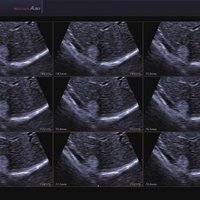

Das Samsung Accuvix A30 ist ein hochwertiges Ultraschallsystem, das mit seiner 3D-Technologie herausragende Ergebnisse ermöglicht. Das Sonographiegerät besitzt 5 Sondenanschlüsse und ist mit 20 unterschiedlichen Schallköpfen kompatibel. Mit dem A30 können Schallköpfe vom Typ Konvex, Mikrokonvex, 3D-Konvex, CW, Phased Array, Linear und Endokavitär verwendet werden. Bei zwei der Sonden handelt es sich um S-VUE Ultraschallsonden, die durch ihre höhere Bandbreite noch feinere Scans erzeugen.

Das Ultraschallsystem hebt sich besonders durch seine 3D-Technologie wie die Face Auto Detection für detaillierte Ultraschallbilder von Föten oder das Volume Shade Imaging, das sich auf die lebensnahe Darstellung von Schattierungen und Hauttönen fokussiert, ab. Mit weiteren wertvollen Technologien wie dem ElastoScan™ werden Tumore schneller erfasst und durch die HD Volumen Bildgebung sowie das DMR+™ eine erstklassige Bildqualität erzielt.